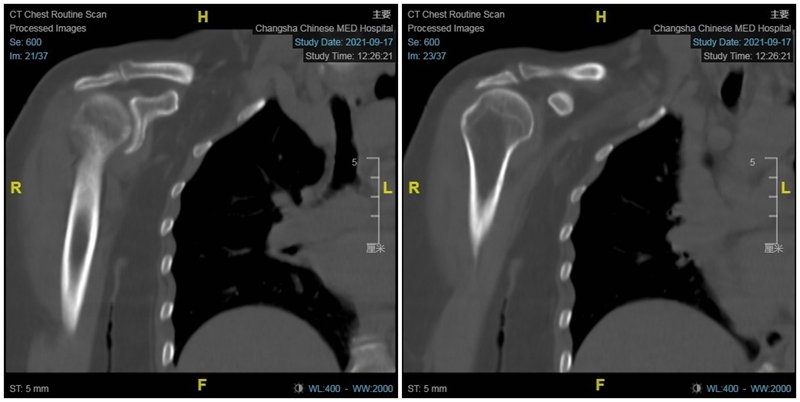

65岁女性,无明显诱因出现右肩疼痛、活动受限1年,外伤后加重2个月入院。术前右肩典型“假性瘫痪”,功能状态如图所示:

术前影像学检查示肱骨头向上移位,关节盂、肩峰和肱骨头退行性改变,典型肩袖撕裂性骨关节病(CTA)改变。